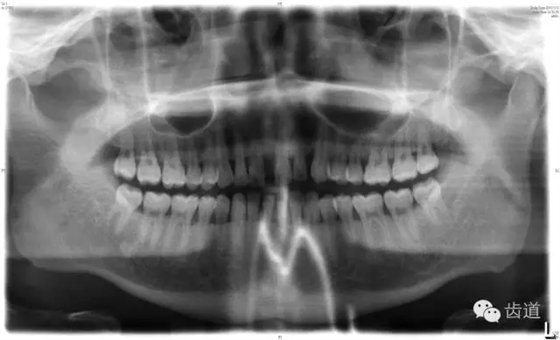

6、輔助檢查

X線:根尖片、曲面斷層片(牙槽嵴頂,水平垂直吸收,程度)